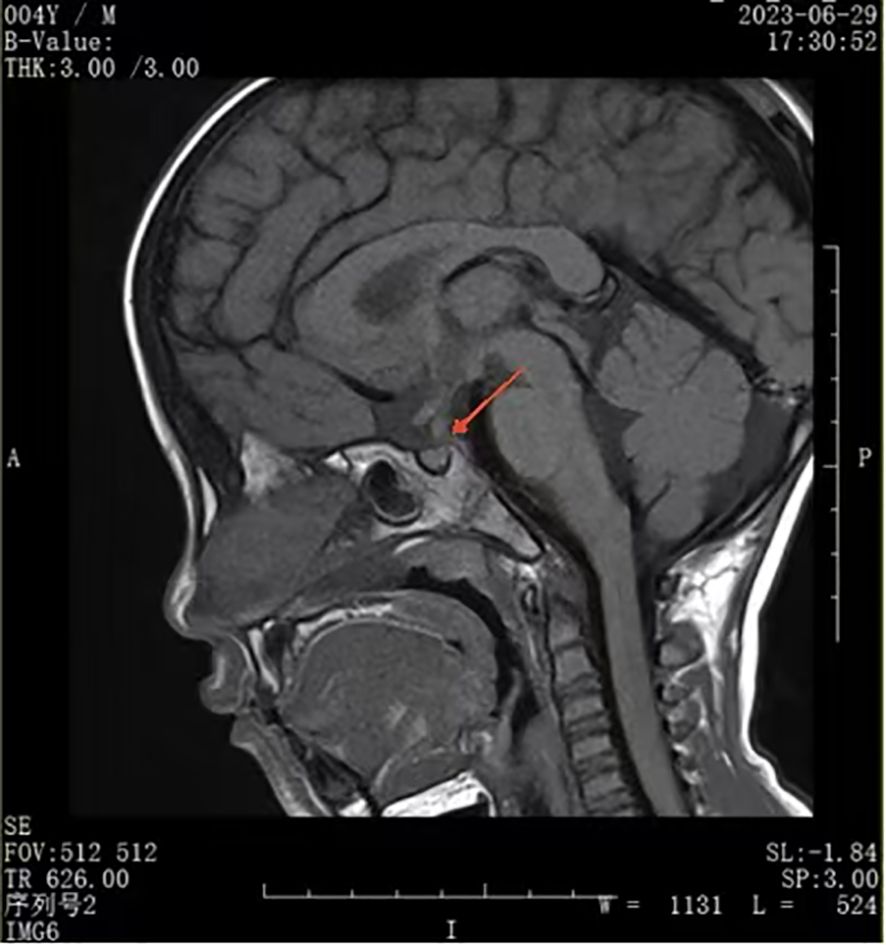

Rationale: SARS-CoV-2 infection can directly and indirectly affect the nervous system, including the hypothalamus and pituitary, and potentially cause IgG4-related hypophysitis. Patient concerns: A 4-year-old Chinese boy presented with arginine vasopressin deficiency (AVP-D, previously called 'central diabetes insipidus') and significant growth retardation. MRI indicated thickening of the pituitary stalk and alterations in the posterior pituitary. Diagnosis: The boy experienced polydipsia, polyuria, and enuresis 4 months after infection by SARS-CoV-2 and 2 months prior to presentation in June 2023. The diagnosis was IgG4-related hypophysitis, AVP-D, and growth hormone deficiency. Treatment with glucocorticoids and desmopressin led to significant resolution of symptoms and normalization of pituitary morphology. However, a second SARS-CoV-2 infection was followed by recurrence of polydipsia, polyuria, and thickening of the pituitary stalk. This recurrence led to a final diagnosis of IgG4-related hypophysitis caused by SARS-CoV-2 infection. Interventions: Glucocorticoids and desmopressin alleviated the AVP-D. Growth hormone and a diet and exercise plan were recommended to manage his short stature. We plan to conduct a functional assessment of the gonadal axis after he is 6 years old. Outcomes: After 18 months, the polydipsia and polyuria were controlled, and an MRI showed significant thinning of the pituitary stalk. This is the first reported case of lgG4-related hypophysitis in a Chinese boy infected with SARS-CoV-2. Lessons: We successfully controlled clinical symptoms, but further follow-up observations are needed to assess recovery. Although the role of SARS-CoV-2 infection in this patient's condition is only suggestive, other reports have described a relationship between SARS-CoV-2 infection and lgG4-related hypophysitis.